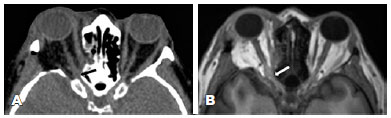

A 38-year-old woman, who tested positive for human immunodeficiency virus, developed thyroid eye disease with left eye proptosis (Hertel 14/18 mm) and upper eyelid retraction (MRD1 = 5 mm OU). Her visual acuity was 20/20 OU. She underwent a deep left lateral orbital decompression. After the procedure, slight bleeding was noted from a temporalis muscle; hence, a Penrose drain was inserted into the lateral space of the orbit. The patient had no history of coagulopathy and was not taking medications that could interfere with blood clotting. On postoperative day 1, she only had light perception on the operated eye. CT and MRI revealed a lateral orbital hemorrhage compressing the optic nerve at the optic canal (Figure 2). During the 1.5-year follow-up, her visual acuity never recovered despite the initiation of intravenous steroid therapy immediately after surgery.

02-fig02.jpg)

To our knowledge, no study has reported vision loss caused by apical bleeding after orbital decompression, wherein a small volume of blood compresses the optic nerve on its entrance in the optic canal. With both MRI and CT, the blood present in the orbital apex caused blurring of the orbital fat between the optic nerve and the muscular cone. CT can distinguish blood from edema because blood has higher Hounsfield units (mean = 60) than fluid (mean = 0)(12).